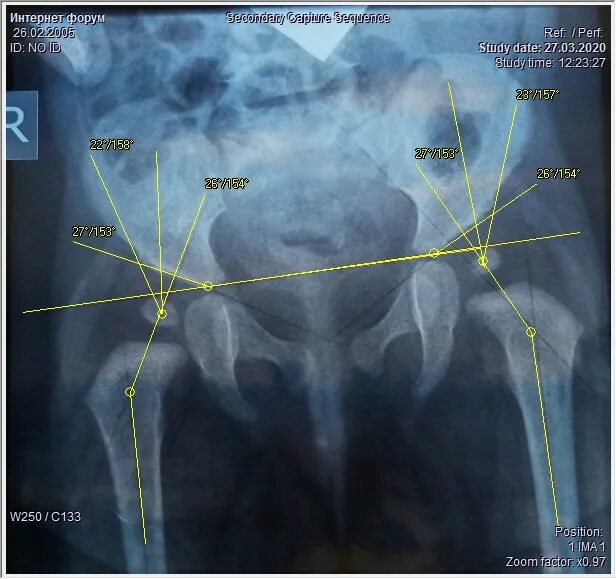

Дисплазия тазобедренного сустава мкб 10